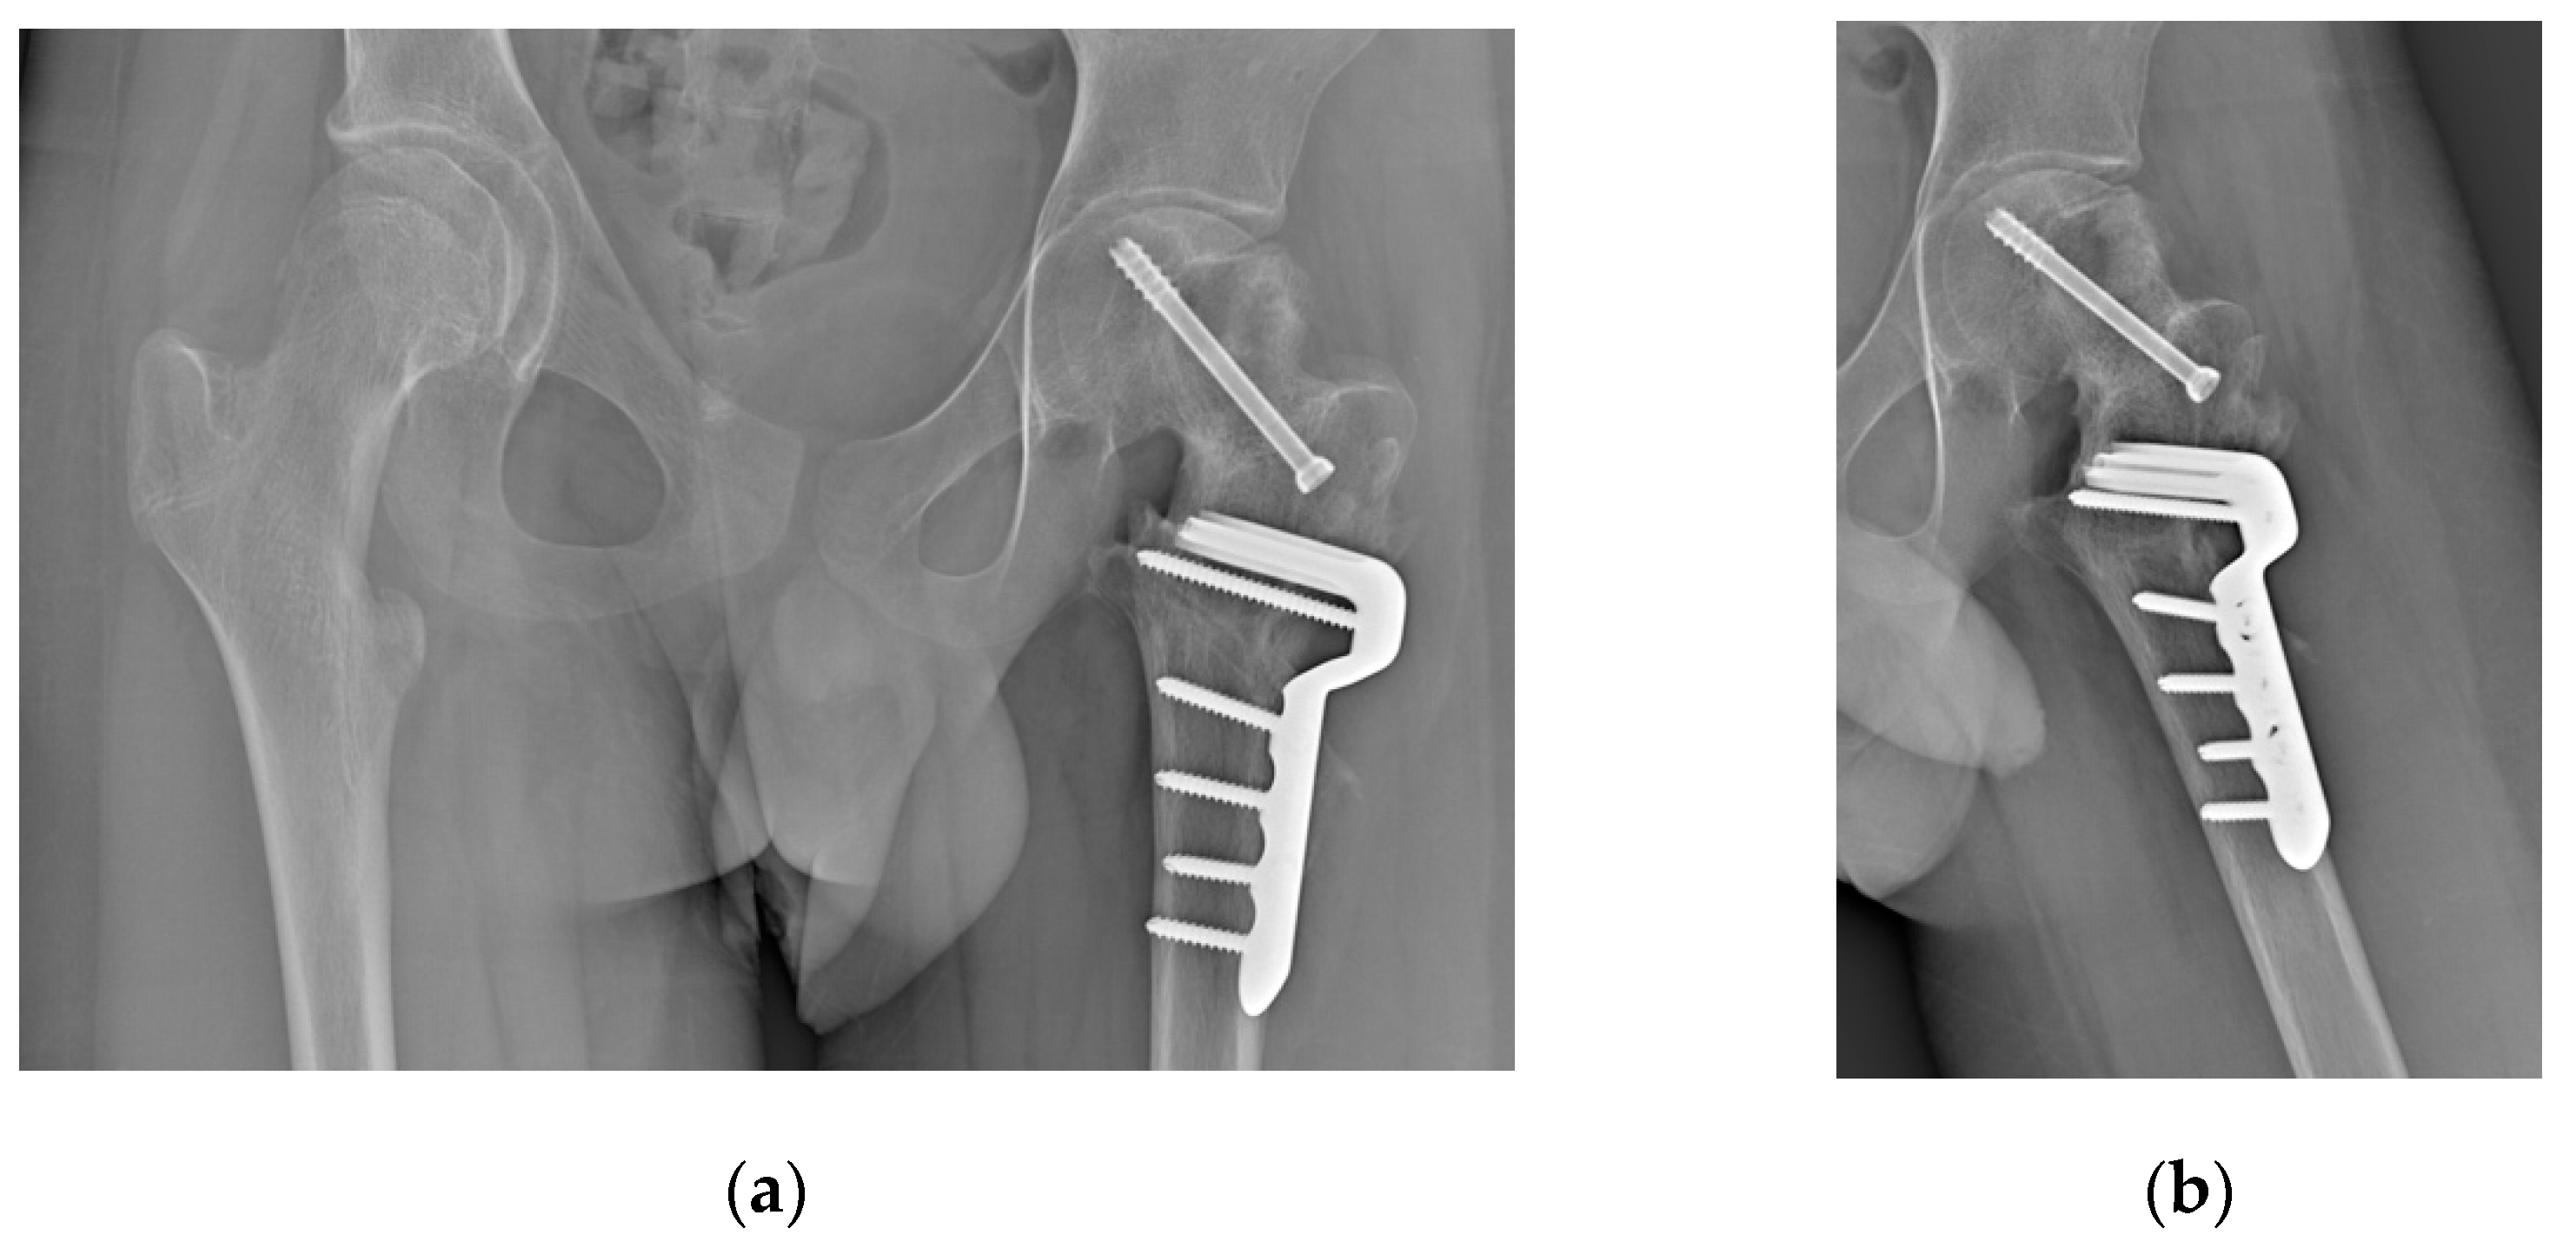

A 15-year-old male with Autism Spectrum Disorder (ASD) sustained a skiing injury, resulting in a Delbet type III basicervical femoral neck fracture (Figure 1a). He had a BMI of 18.6 (28th percentile by age and sex) with height 177 cm and weight 55 kg. Treatment involved closed reduction and internal fixation using a Dynamic Hip Screw (DHS) plate and an additional free cannulated screw (Figure 1b). Intraoperative fluoroscopic images showed satisfactory reduction on the anteroposterior plane with a residual 15° retroversion deformity on the lateral plane. The reduction was deemed satisfactory, and at a one-month follow-up, progressive fracture healing was noted (Figure 1c). However, three months later, radiographs revealed worsening slippage (Figure 1d). Although initially overlooked, mild slippage was evident on radiographs taken one month post-injury, with residual pain attributed to the recently healed fracture. As the condition worsened, the patient was referred to a tertiary referral center for pediatric orthopedics for further evaluation.

Figure 1. (a) Radiograph after trauma showing a Delbet type III femoral neck fracture; (b) Radiograph after open reduction and internal fixation surgery; (c) Radiograph at one-month follow-up showing signs of mild SCFE; (c) Radiograph at three-months follow-up showing worsening SCFE.